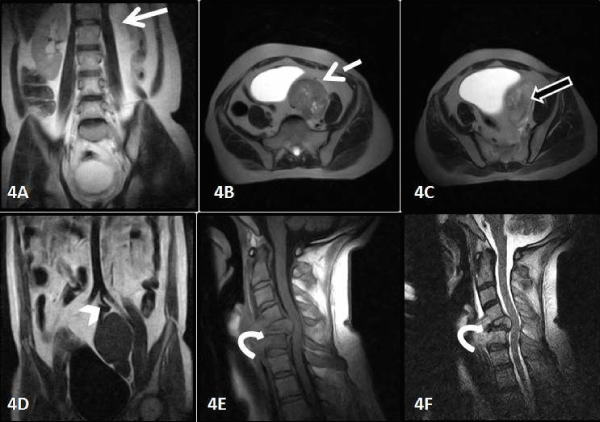

| Figure 4: Magnetic resonance imaging confirming the findings with empty left renal fossa (white arrow), mass in ectopic left kidney ( dotted arrow), normally visualized parenchyma of left kidney( black arrow with white outline), ectopic kidney supplied by left common iliac artery and vertebral metastasis in C5 vertebral body with cord compression. |